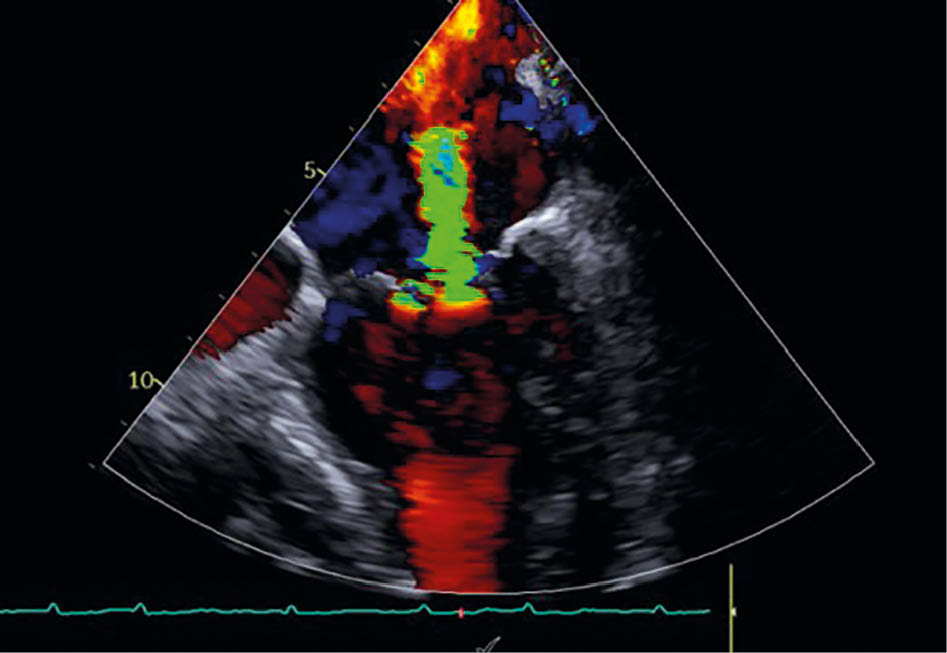

Abbildung 3a: Mitralklappeninsuffizienz in TEE vor der Behandlung

Eine 84-jährige Patientin mit bekannter Herzinsuffizienz bei erhaltener Pumpfunktion (HFpEF, LVEF 50 %) und symptomatischer Belastungsdyspnoe (NYHA III: Treppensteigen nur mit Einschränkungen möglich) wurde in der Klinik vorstellig. Die transthorakale Echokardiographie ergab eine schwere sekundäre Mitralklappeninsuffizienz (effektive Regurgitationsfläche EROA: 0,5 cm2) bei ausgeprägter linksatrialer Dilatation (Volumenindex 64 ml/m2). Als weitere Diagnosen sind eine arterielle Hypertonie und chronisch permanentes Vorhofflimmern bekannt. Die konservative Therapie bestand aus ACE-Hemmer, Betablocker, Schleifendiuretikum und SGLT2-Inhibitor. Trotz maximaler medikamentöser Therapie persistierte eine relevante Symptomlast.

Im interdisziplinären Herzteam wurde nach Ausschluss einer proportionalen MI mittels EROA in Relation zum linksventrikulären enddiastolischen Volumen (LVEDV) und fehlender Eignung für TEER aufgrund suboptimaler Koaptationshöhe die Entscheidung zur CARILLON®-Implantation getroffen.

Prozedur

Die Implantation eines 60-mm-Carillon®-Systems erfolgte unter fluoroskopischer und TEE-gestützter Kontrolle nach vorheriger intraprozeduraler Größenauswahl und Anpassung in Analgo-

sedierung. Die Implantation verlief komplikationslos. Eine angiographische Kontrolle schloss eine relevante Kompression des RCX und der RCA aus. Die Interventionsdauer betrug 45 Minuten, die Durchleuchtungszeit 11 Minuten.

Ergebnisse

Postinterventionell zeigte sich echokardiografisch eine Reduktion der MI auf Grad 1 mit deutlicher Abnahme des EROA auf 0,1 cm2. Die Patientin berichtete bereits am ersten postinterventionellen Tag über eine deutliche Besserung der Dyspnoe. Die Entlassung erfolgte am zweiten postprozeduralen Tag unter stabilen hämodynamischen Verhältnissen. Die strukturelle Nachsorge ist über den niedergelassenen Kardiologen in enger Zusammenarbeit mit der kardiologischen Klinik organisiert (TTE-Kontrollen nach 1, 3 und 6 Monaten, Laborparameter, 6-Minuten-Gehtest [6MWT]).